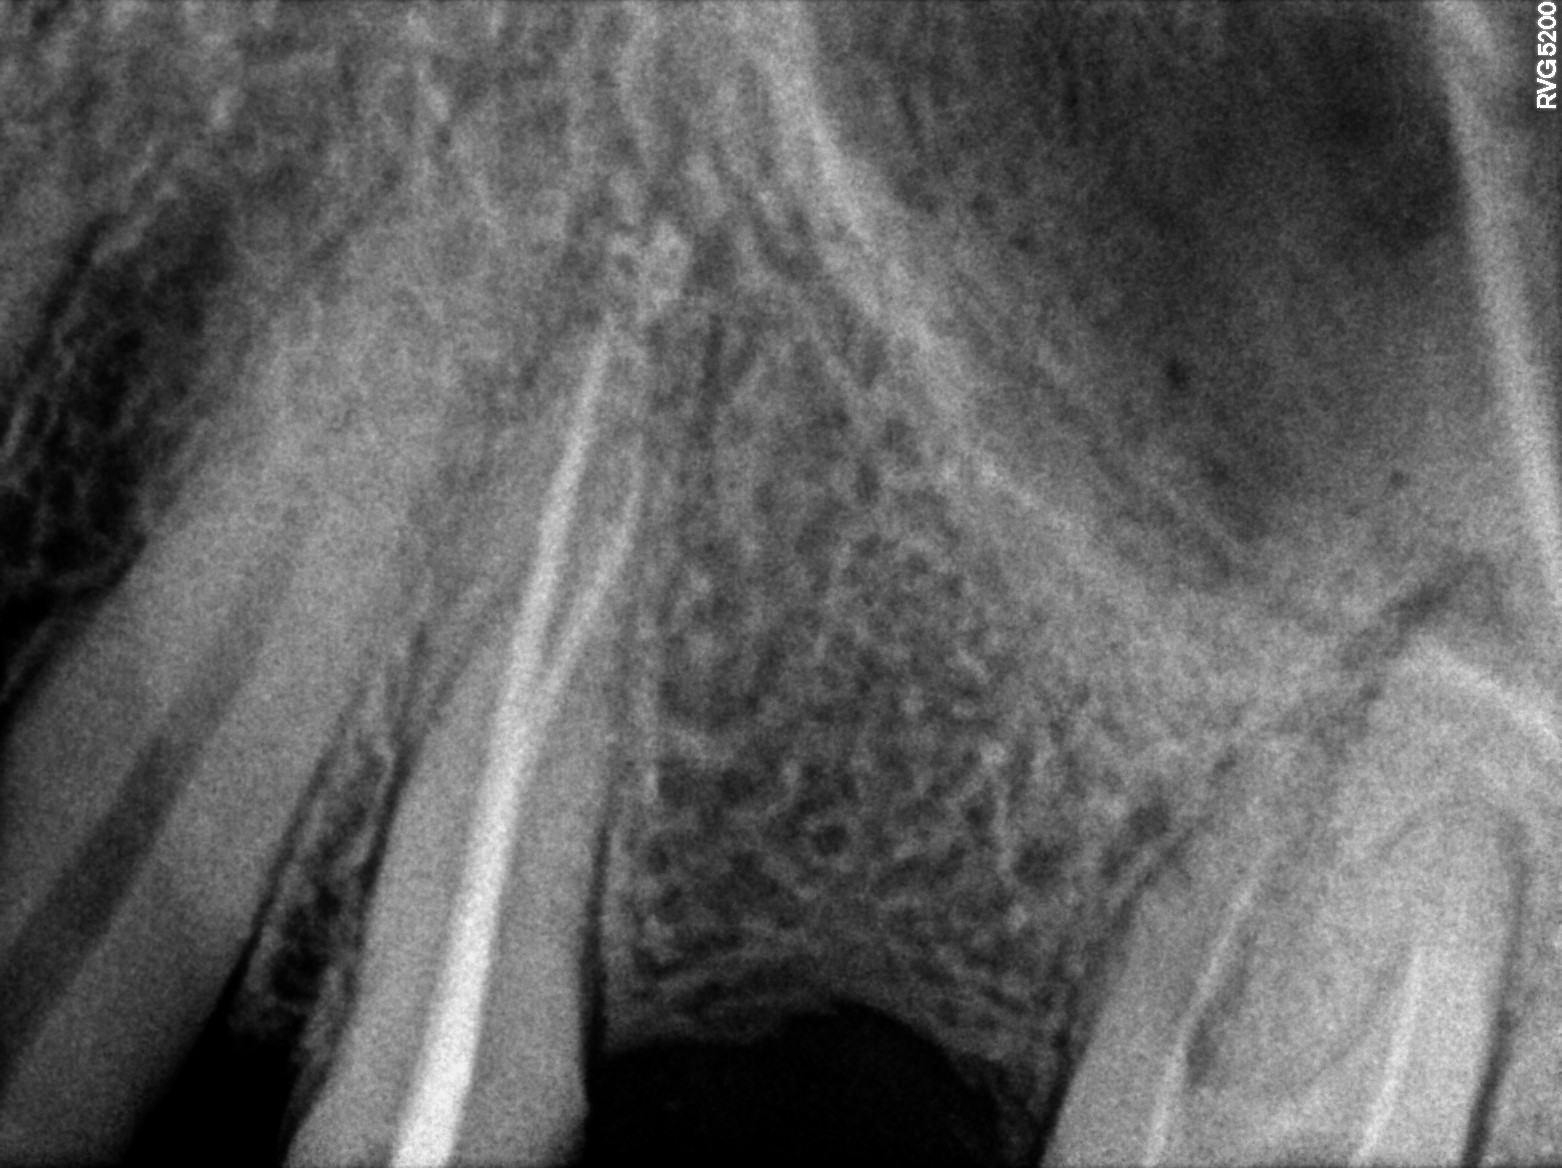

Dental Radiographs FHIR: DocumentReference · LOINC 24641-7

2 (1).jpg

24641-7